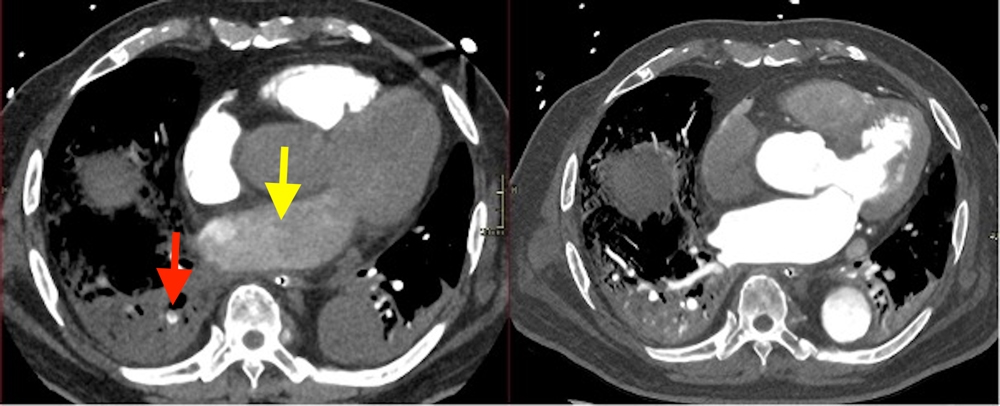

Le Pr Gilbert Ferreti, spécialiste en imagerie thoracique, détaillera les modifications attendues liées à l’âge au niveau des différents compartiments anatomiques du thorax : réticulations sous-pleurales, augmentation du rapport broncho-artériel ou encore épaississement de la paroi bronchique. Les scanners réalisés dans le cadre d’une suspicion d’embolie pulmonaire ont un rendement diagnostique plus faible dans cette population, mais permettent souvent de mettre en évidence des diagnostics différentiels. Les ajustements techniques nécessaires pour obtenir un angioscanner de qualité seront précisés (fig. 2), avec un focus sur l’importance d’accorder du temps pour obtenir la coopération des patients.

Fig 2 : Protocole d’angioscanner thoracique inapproprié. Recherche d’embolie pulmonaire (EP) chez un homme âgé de 73 ans. (a) Fausse embolie pulmonaire (flèche rouge) liée à une opacification incomplète car trop précoce de l’artère pulmonaire (OG vide de contraste (flèche jaune)). (b) Après nouvelle injection avec départ plus tardif de l’acquisition, remplissage correct des branches de l’artère pulmonaire.